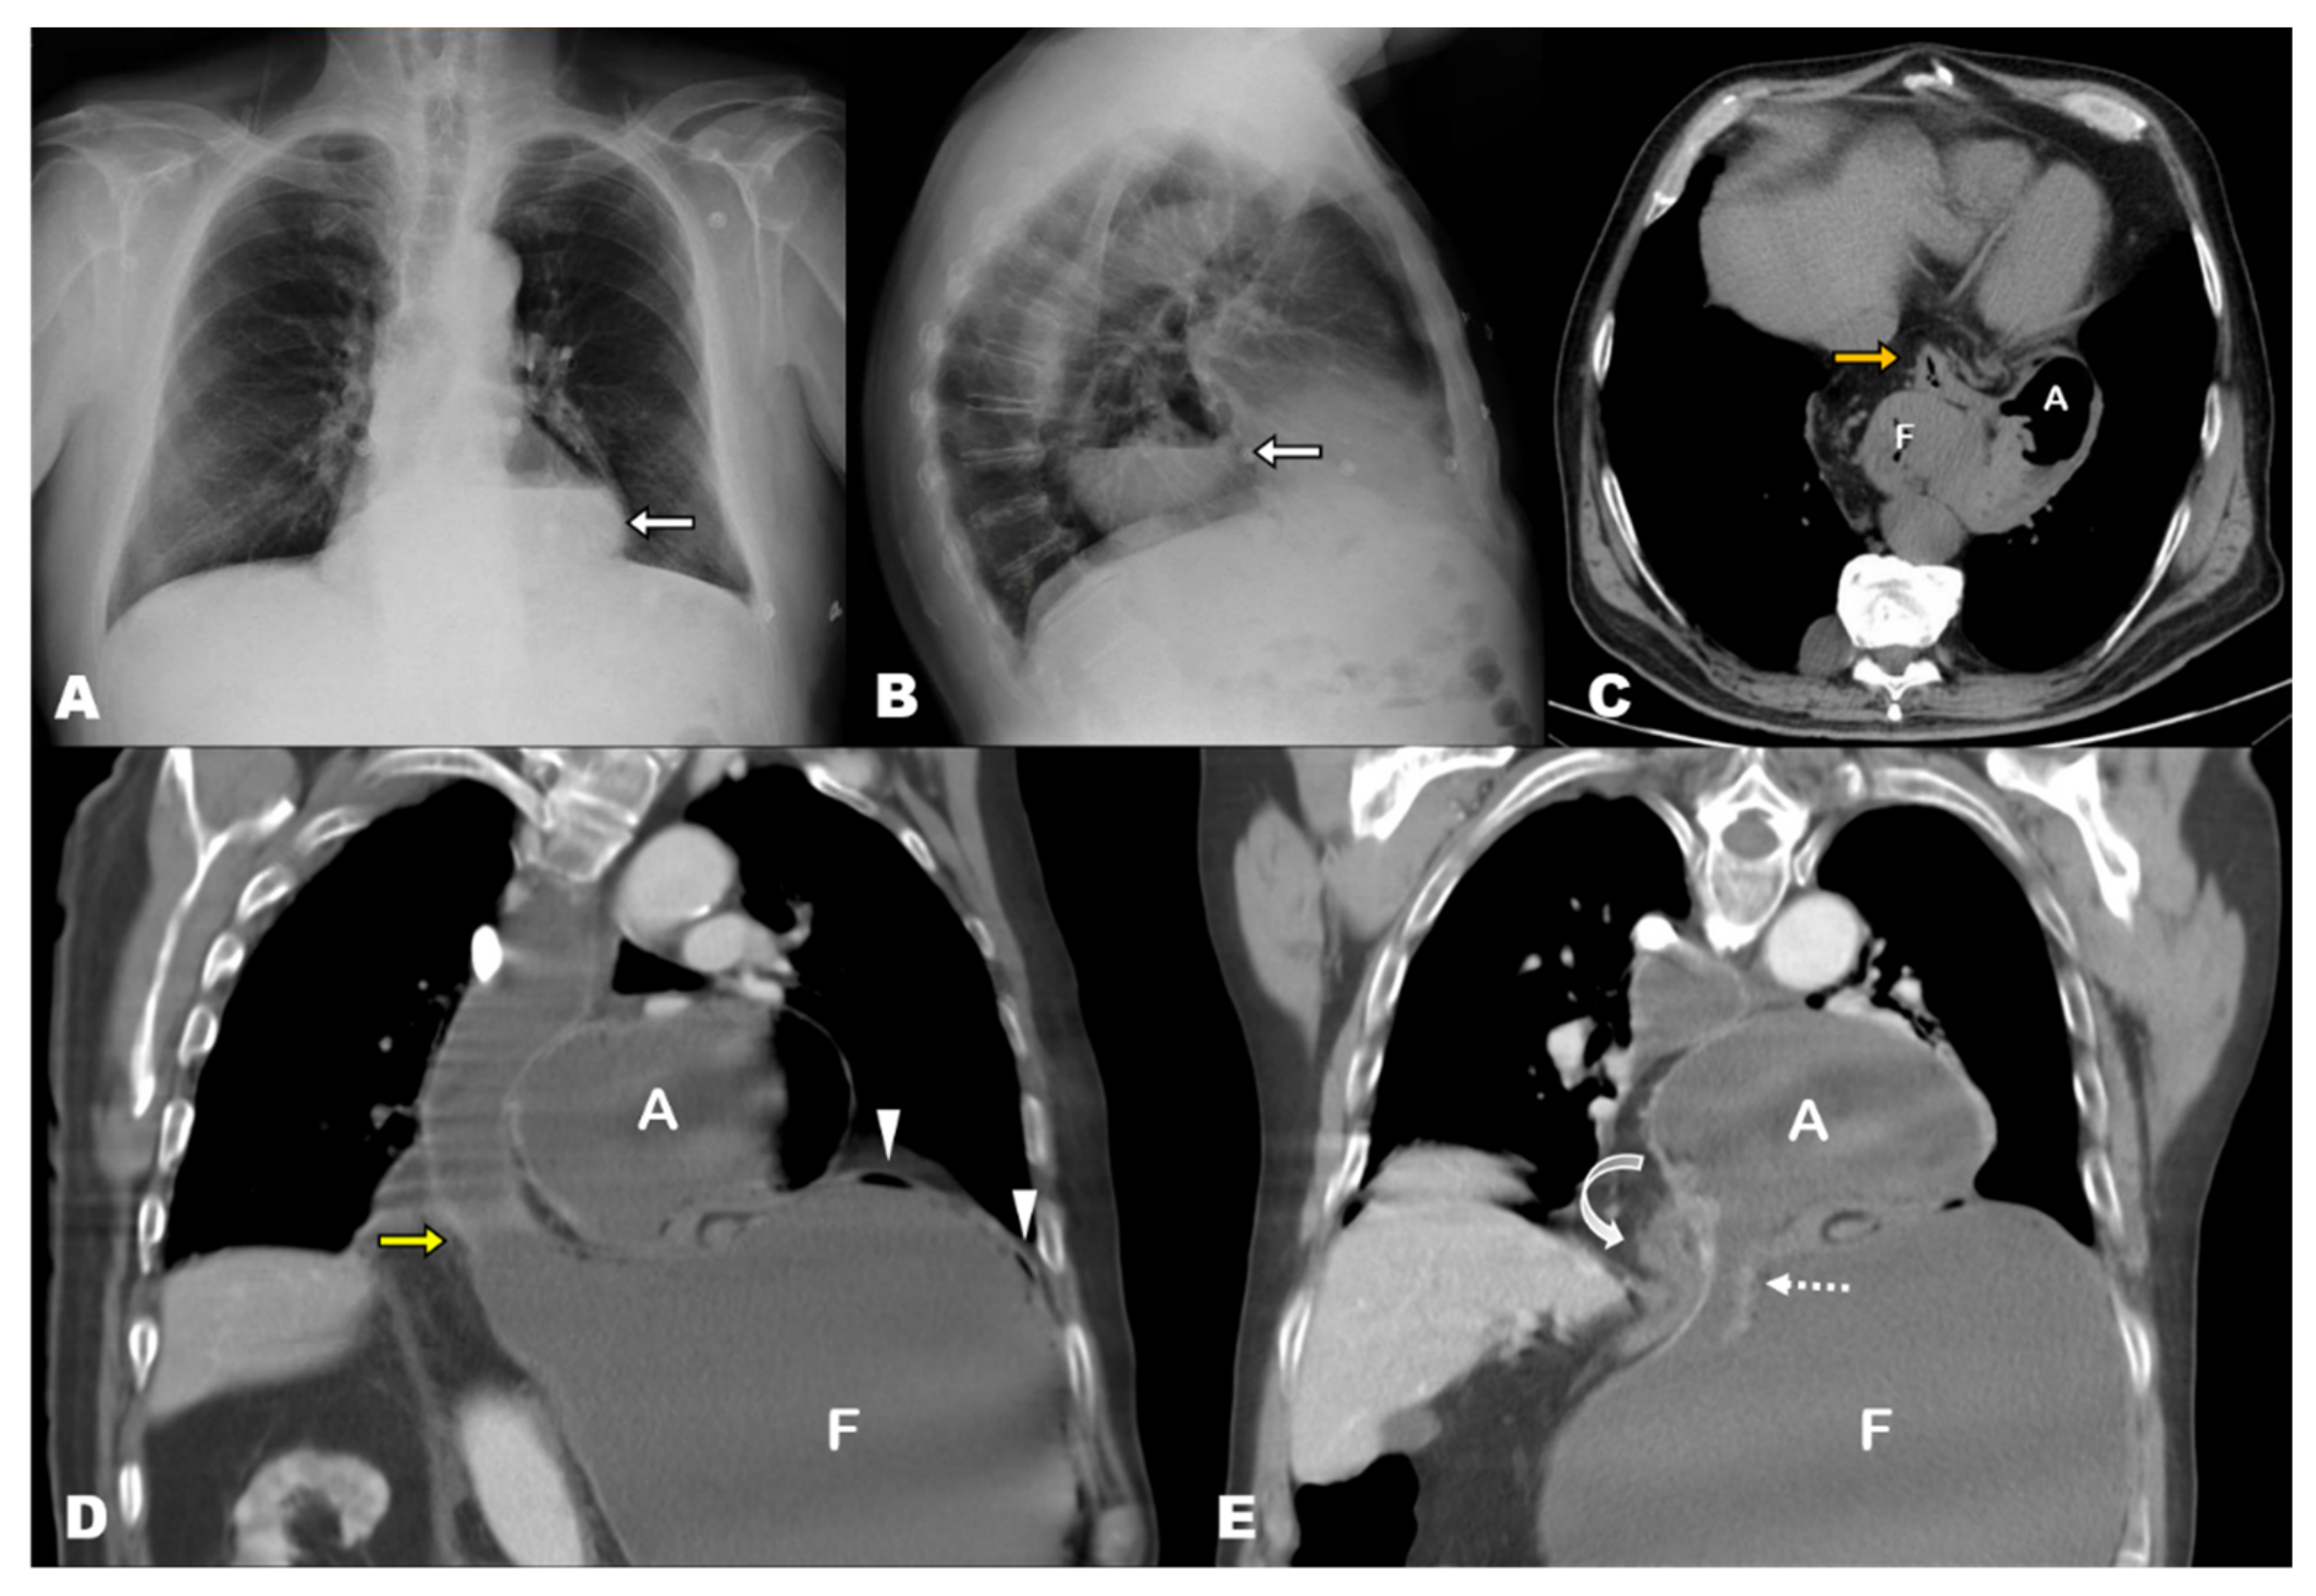

3. Results